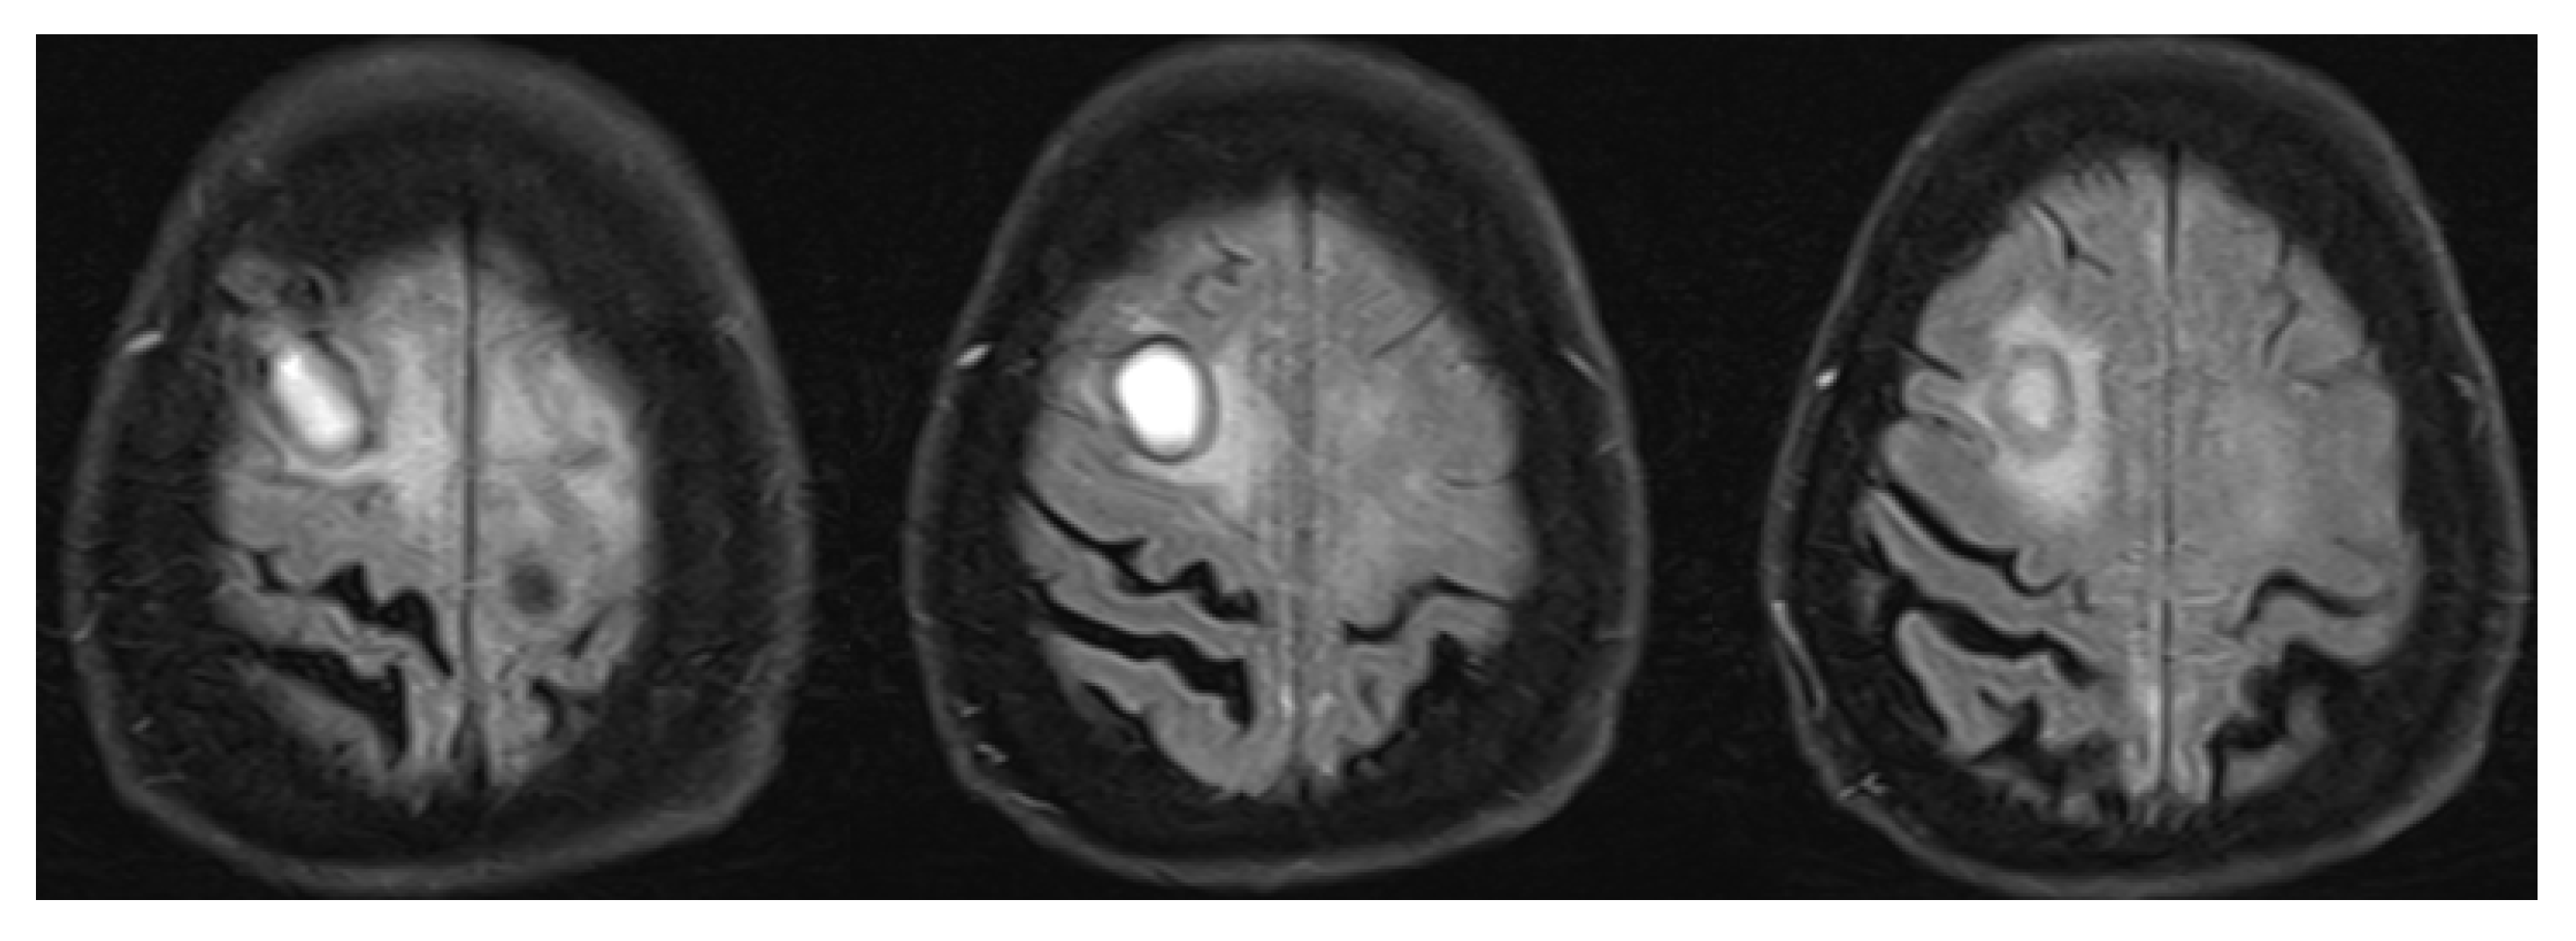

3.2. Inflammatory Cerebral Amyloid Angiopathy (ICAA)